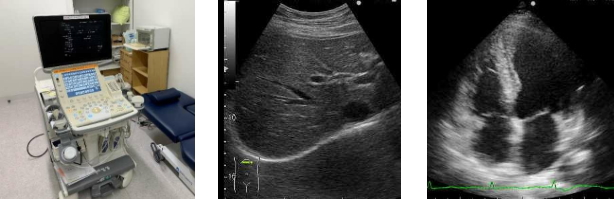

○ 超音波検査

エコー検査とも呼ばれ、超音波を用いて体の中を観察する検査です。

検査する箇所にゼリーをつけ、その上からプローブと呼ばれる機械を押し当て検査を行います。

超音波を用いた検査のため被ばくはありません。